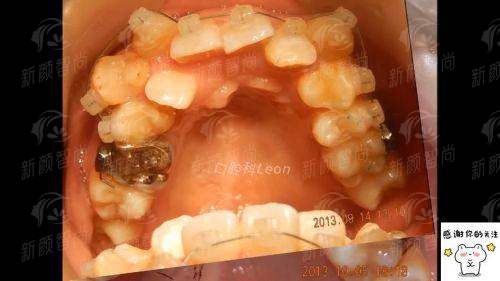

牙齿不整齐有诸多隐患,金属自锁矫正是高效舒适之选。甘肃兰州诺贝尔口腔门诊部采用美国3M原装进口矫治系统,技术优势明显。文章介绍了其与传统矫正区别、矫正流程,还提供了多种预约方式。该门诊部设备先进、团队专业,能为患者带来理想矫正效果,助您拥有整齐健康牙齿。